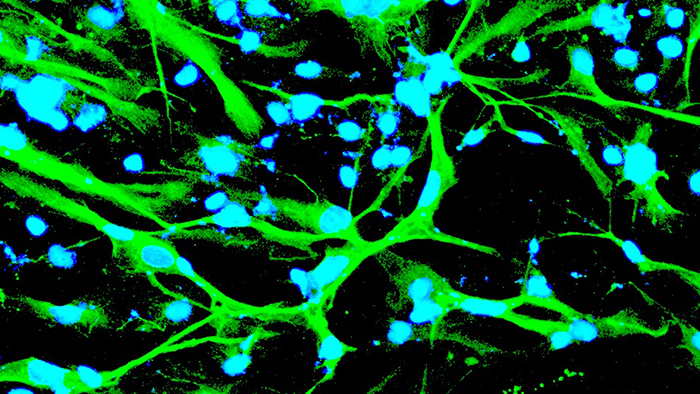

Researchers are peering more intensely down into the molecular and cellular foundations of human biology to study the evolution many of the world’s more debilitating diseases — and potential remedies for them. This high-precision approach is being employed by biomedical engineers and other health and medical experts like Fulton Schools Associate Professor David Brafman. He is exploring the molecular clues in stem cells, and ways to reprogram them, to attempt to produce knowledge that could lead to prevention or a cure for Alzheimer’s disease. Among other things, Brafman is experimenting with cutting-edge gene editing technologies in pursuit of his goal.